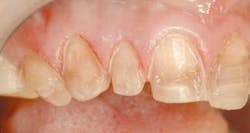

In fig. 5, we can see how our patient presents before we begin our treatment. Using the guidelines above, we can now see what corrections we need to make.

Our patient desired a vast improvement in the color of her teeth. We can all agree these teeth are rather dark and detract from the beauty of her smile. Part of the reason is due to the underlying tetracyline staining of the teeth. The other reason is simply that there were not enough teeth prepared to significantly change the color.

One of the most common mistakes dentists make when providing porcelain veneers for their patients is to do six teeth, canine to canine. I have always wondered why this trend was started. Obviously, smiles do not stop at the canines. As a result, the majority of these cases will exhibit a "negative" buccal corridor, meaning the sides of the smile will appear darker. There is no width to the smile. It can look like the teeth "sink in" lingually.